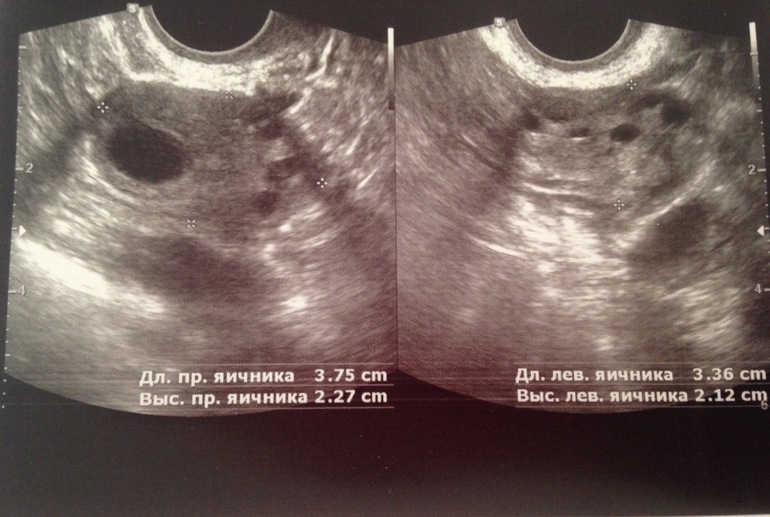

Добрый день,девочки.Дано:35ДЦ,задержка уже ну как минимум 3-5 дней...Тесты отрицательные ,на 23 ДЦ нашли в эндике включение 0,34 мм.Овуляцию чувствовала на 15-17 дц (точно не помню но не раньше ,не позже)резкая боль в ЛЯ,чуть розово-красных выд-ий.Сегодня УЗИ :Эндик 7мм(однородный)в ПЯ ЖТ 13мм??На 90%ЖТ как сказал врач.А мне вот не кажется,что это похоже на ЖТ,но я не врач,хз.В ЛЯ только фоллики..И никакого образования в Эндик нету(специально не сказала ,что там что-то находили,для чистоты эксперимента)Но когда будут М не сказали,ЖТ или нет не понятно.Да и чувствовала я 💯 процентов слева!!!Прилагаю фото,где два снимка -это сегодня ПЯ и ЛЯ,где один с точкой это включение -на 23 дц,ну и последний сегодня эндик .Как думаете,ЖТ???

Я конечно не врач, но столько уже насмотрелась на эти мнимки узи! Как по мне так в левом яйичнике очень похоже на фолликул, а не на жт! У жт контур не четкий, оно как облачко, я их сама не определяю, зато на фолликулы глаз наметан) это ьакой ровный черный шар! Хотите скину фотку как мое жт выглядит?

Вот-вот.Толтко это ПЯ))Да ,киньте плиз ,а то я не дома,на свои не могу снимки прошлые глянуть

это фолликул 18мм

это желтое тело.

Я лично вообщн не понимаю как она там его увидела)) но она уверенно сразу сказала! А фолликулы я сама на экране видела и понимала что это они)

Ну да,тут на фоллик точно не похоже )))А у меня дыра блин,чёрная))Если у меня это фоллик,а уже 35 дц...то я грущу:(и вообще не понимаю как так

А мне от этого,что я и не жду беременность,потому что мы предохраняемся))Хоть и ППА,но все же осечек небыло ...А вот циклы мне по 50 дней точно не нужны.Да и причём тут Б?Вопрос мой в том,похоже это на ЖТ или это фоллик!Т.к.врач сам не дал 100% ,что это Жт.Если ЖТ,то буду ждать М,а если нет,то дюфастон мне в помощь!

фолик

и из него желтое тело